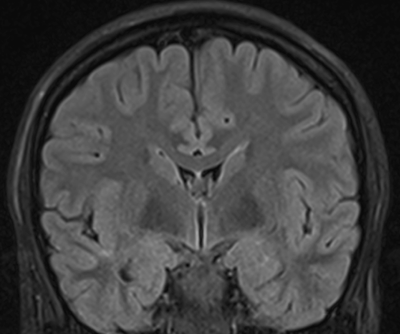

Temporallappen er afgrænset opad til mod lateral fissuren (fissura Sylvii), posteriort mod occipitallappen, postero superiort mod parietallappen, inferiort mod gulvet af fossa crani media, og medialt mod de præpontine cisterne og mod hjernestammen posteriort. Den mesiale del af temporallappen er beskrevet mere i detaljer i siden om Hippocampus. Husk at gyri og sulci er "koncepter", de er ikke altid kontinuerlige, en gyrus kan således krydses af en sulci og stadig være den samme på den anden side af den pågældende sulci, eller splittes i to parallelle som tilsammen udgør en navngiven sulci. I figurene til høje er angivet såvel de normale gyrus navne, som de mere enkle T1-T5, T6 udgøres af hippocampus. Lateralsiden af temporallappen udgøres af tre gyri adskilt af to sulci. Gyrus superior (T1) og gyrus medius (T2) adskilles af sulcus superior, mens gyrus medius og gyrus inferior adskilles af sulcus inferior. Den inferior flade af temporallappen, som hviler på gulvet af fossa crani media, udgøres af 3 gyri adskilt af to sulci. Den mest lateral gyrus er gyrus inferior (T3) som er afskilt fra gyrus fusiforme (T4) af en inkomplet sulcus occipito-temporale, mens gyrus fusiforme (T4) er adskilt fra gyrus parahippocampale (T5) af sulcus colatteralis. Dybden af sulcus colatteralis prominere ind i temporalhornet af lateralventriklen som prominentia colatteralis. Den superiore flade af temporallappen grænser op mod Insula inferiore halvdel. Den forreste del af denne flade er konkav og matcher den anteriore inferiore konvekse form af Insula, mens den posteriore supriore flade en med plan. Denne forskel kan tydligt erkendes på coronale MR-skanningssnit. Overgangen mellem den konkave og den plane den af temporallappens superiore flade markere lokalisationen af Heschel's gyrus. Heschel's gyrus har et skråt forløb fra antero-lateralt til postero-medialt. Lateralt findes Heschel's gyrus lige overfor gyrus postcentral i parietallappen adskilt af lateralfissuren. Følges Heschel's gyrus medialt posteriort peger den mod antrum af ventrikelsystem lige posteriort for thalamus. Den mesiale flade af temporallappen er en konkav flade som omgrænser hjernestammen.